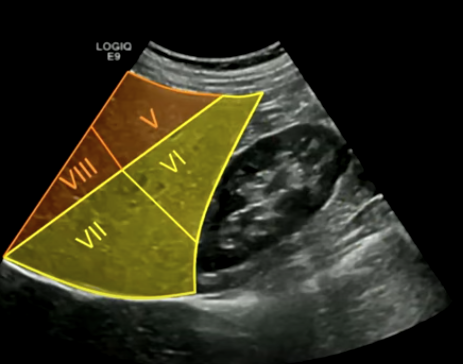

Kidney (lateral view): Segments five, eight, six, and seven. The right kidney is located inferior and lateral to the right lobe of the liver.

Kidney (far lateral): Segments five, six, seven, and eight.

right hepatic vein separates 6 and 7 from 5 and 8

Separates segments seven and six from eight and five. The hepatic veins drain directly into the IVC.